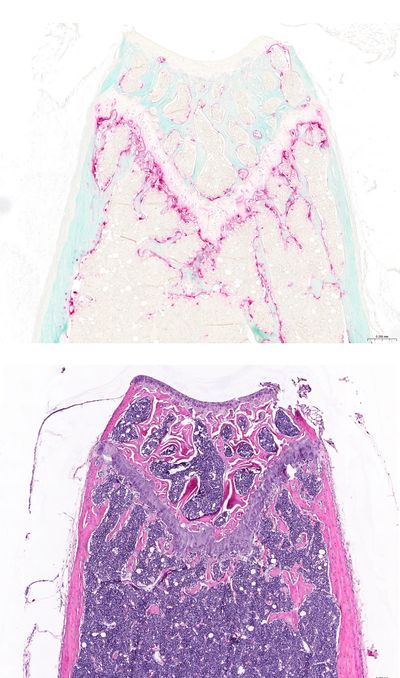

Osteoporosis is a skeletal disorder characterized by compromised bone strength and increased risk of fractures. The ovariectomy (OVX)-induced model is one of the most widely used and reliable animal models for postmenopausal osteoporosis. Removal of the ovaries mimics the hormonal changes that occur after menopause, leading to bone loss and skeletal fragility.

Histology markers:

Representative readouts: